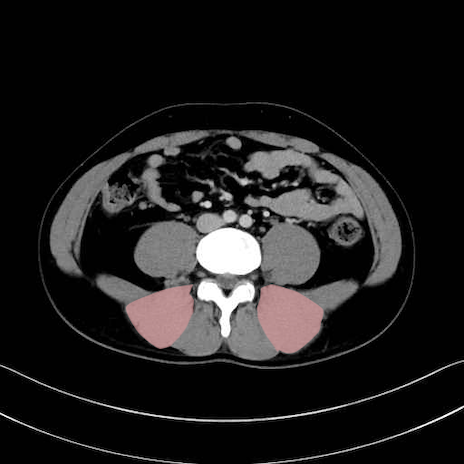

脊柱起立筋 (Erector spinae)

多裂筋 (Multifidus)